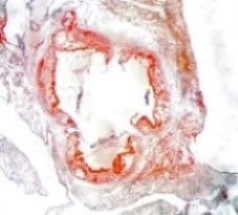

Atherosclerosis Aortic Root Histology Examples

Oil Red-O Staining (fat-soluble dye)